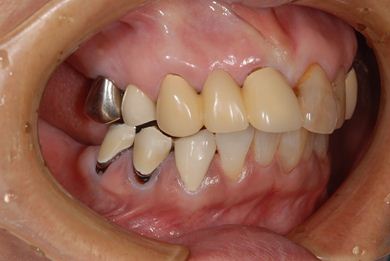

治療前

• 治療前